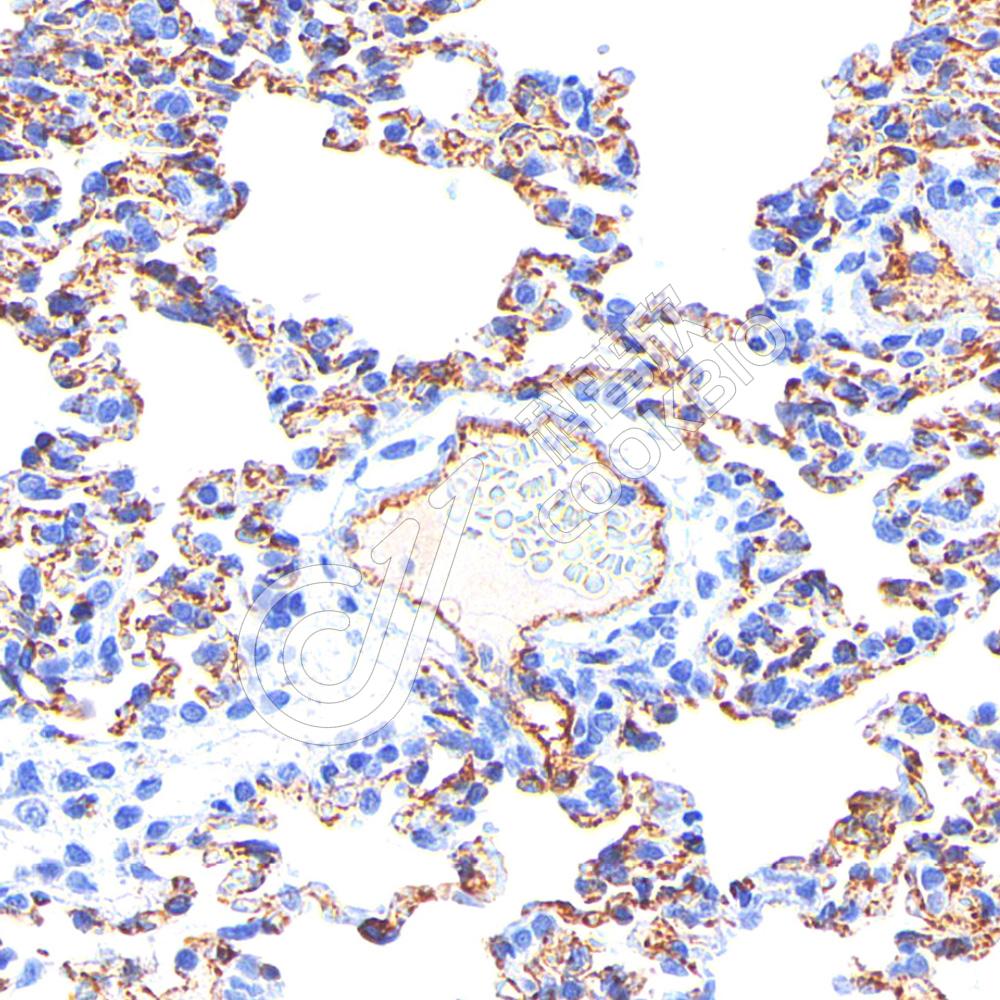

IHC检测CD31蛋白(货号 K2360024).

样品: 大鼠肺, 4%多聚甲醛 (货号KSG1101) 固定12-24小时.

抗原修复: 柠檬酸抗原修复液(干粉, pH 6.0) (KSG1201), 高压锅均匀喷气计时2分钟.

—抗: 1: 800稀释, 4℃ 孵育过夜.

二抗: S-vision免疫组化多聚二抗(山羊抗小鼠), 即用型(货号KB3903), 室温孵育20分钟.

样品: 小鼠肺, 4%多聚甲醛 (货号KSG1101) 固定12-24小时.